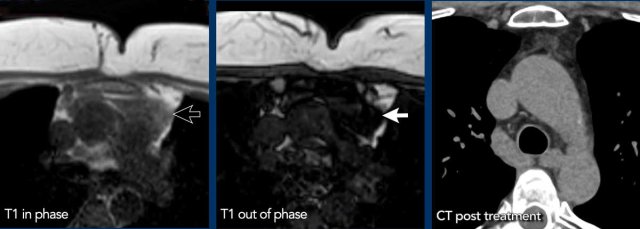

These images are of a 43-year-old male with chest pain.

Images

There is a mass in the prevascular mediastinum.

The border is irregular and the lesion is positive on a PET-CT.

Discussion

The most likely diagnosis was a thymoma, probably invasive or even a carcinoma.

Continue with a preoperative scan two months later...

Two months later a preoperative scan was performed.

It is clear that the lesion is smaller.

However the surgeon decided to resect the lesion anyway and it turned out to be a thymus carcinoma.

We have no clear explanation for what happened here.

There is some reaction in the soft tissues surrounding the tumor on the first scan (arrow).

Maybe there was some inflammation within the tumor and surrounding tissues, which made the tumor look bigger.